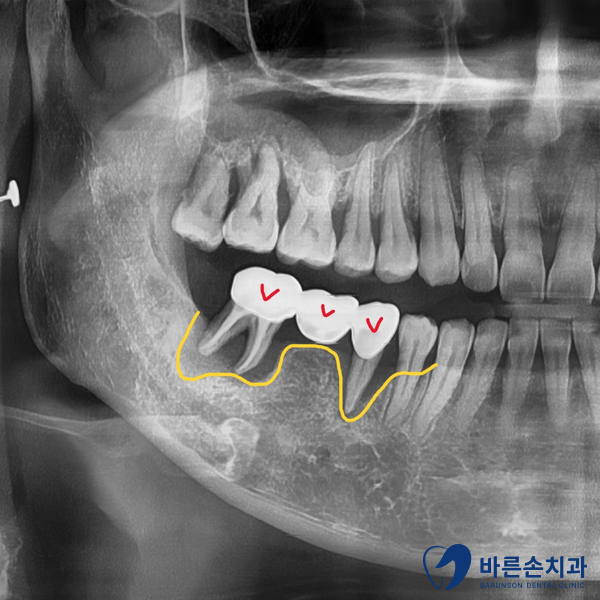

우측 아래 어금니들이 흔들려서 내원하신 환자분 입니다.

위 사진의 노란 선이 현재 치조골의 높이입니다.

치아 뿌리 아래까지 뼈가 내려가 있네요..ㅠㅠ

발치하고 임플란트가 필요한 상황입니다.

가운데 뼈가 있는 부분은 바로 임플란트를 식립했고

바로 앞에 뼈가 내려간 부분은 발치와 보존술(뼈이식)을 하기로 했습니다.